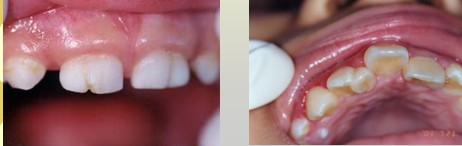

解析: 牙齿萌出过早:乳牙早萌:诞生牙、新生牙

解析: 鉴别:上皮珠 Epithelial pearl (马牙子)

牙齿萌出过早包括:乳牙早萌,诞生牙 Natal teeth和新生牙 Neonatal teeth。

解析: 牙齿萌出过早

牙齿萌出过早的病因不太明了,可能与牙胚距口腔黏膜近、种族有关,其治疗:极松动牙 —— 及早拔除;舌系带创伤性溃疡 —— 调磨锐缘,改变喂养方式。